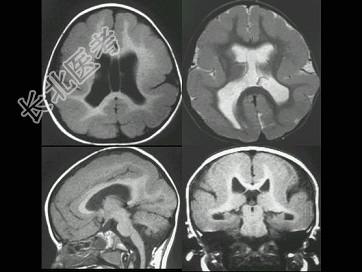

- 单项选择题患儿6岁,自1岁后多次癫痫发作, 药物治疗疗效不明显。如图所示,最可能的诊断为 ( )

A、巨脑回

B、脑裂畸形

C、灰质移位

D、无脑回畸形

E、无脑畸形